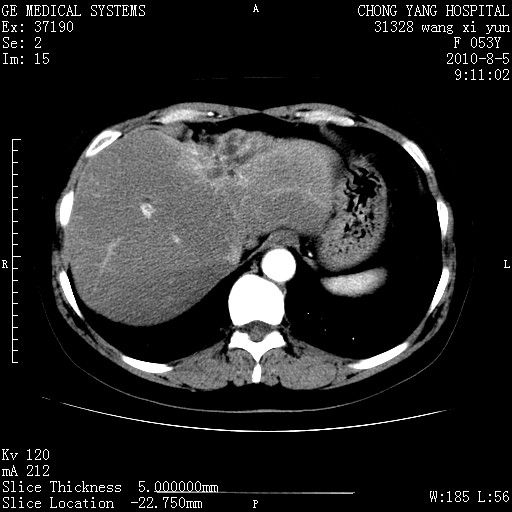

标题: CT28214:F41Y 血尿二十天,建议盆腔平扫加增强。

胆管细胞ca?

1)考虑肝左叶胆管细胞癌。2)脂肪肝。

支持胆管细胞ca。